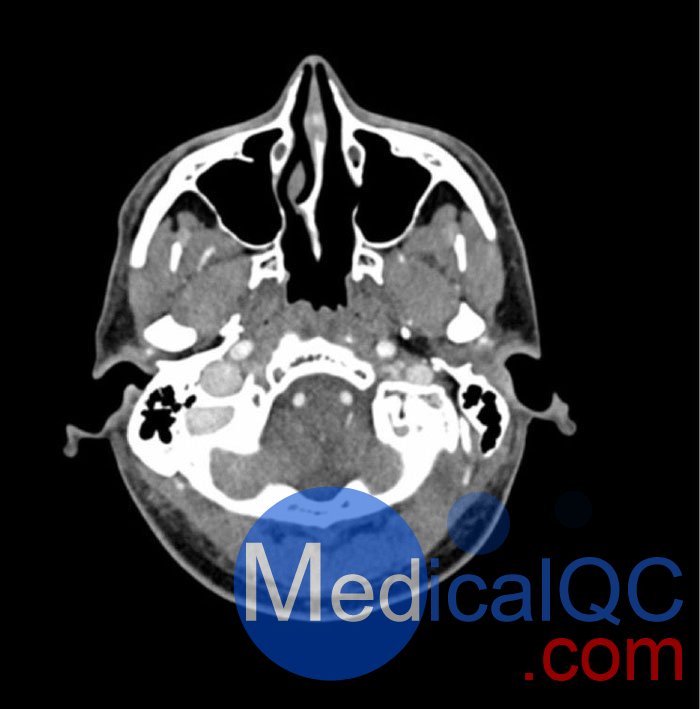

WEK-5005腦血管造影頭模,WEK-5005頭模, CTA AVM頭模模擬動脈期造影劑增強頭部(CT 血管造影)。 它覆蓋枕骨大孔的頂點。

該模型在半卵圓中心有 10 個低對比度病變,右半球有動靜脈畸形。

該體模可用于 CT(包括 CBCT),以評估和優(yōu)化成像性能和人工智能診斷。 它也適用于培訓目的。 該模型提供了血管結構、軟組織和骨組織的詳細而真實的模擬。 空氣空隙充滿了HU為160的約 100 微米的纖維素聚合物復合材料.

WEK-5005腦血管造影頭模,WEK-5005頭模, CTA AVM頭模成像效果圖:

WEK-5005腦血管造影頭模,WEK-5005頭模, CTA AVM頭模成像效果圖